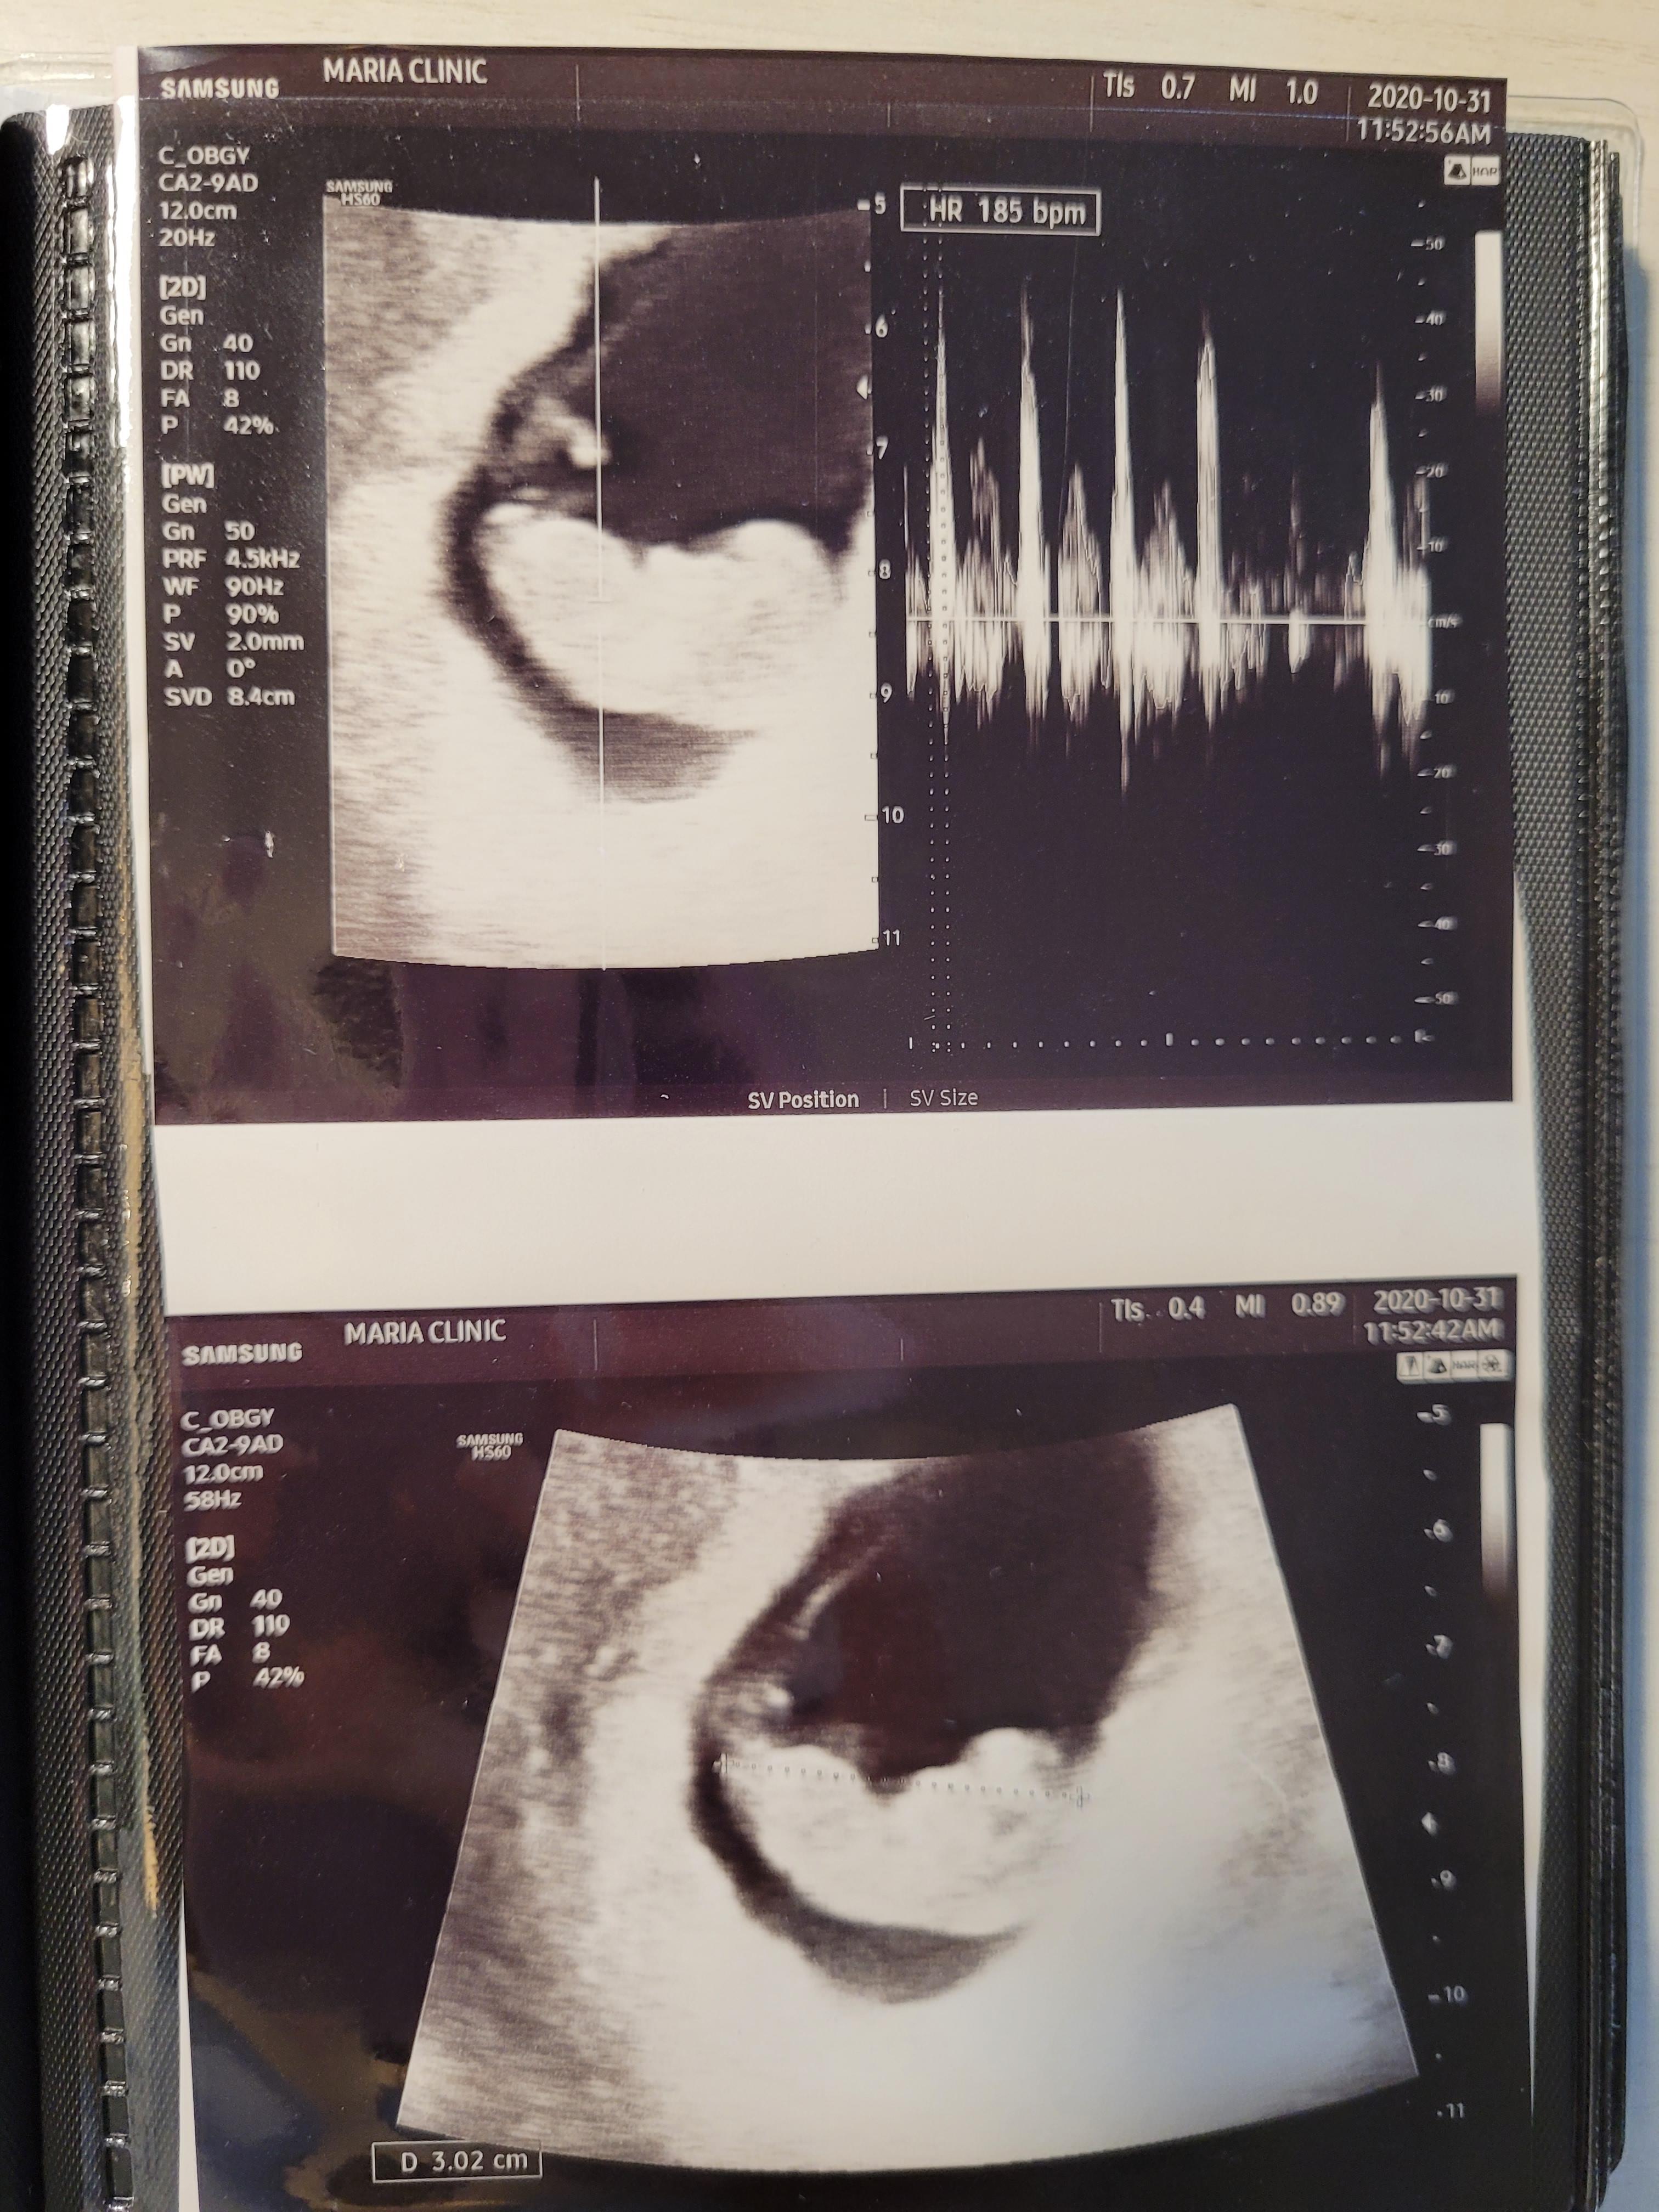

임신 9주 5일 평촌마리아 졸업!!

원래는 10주 0일에 정기검진인데, 9주 0일 월요일에 방문하고 9주 5일 토요일에 다시 방문을 했어요.

남편도 초음파를 같이 보고싶었고, 이제 복직이라 평일에 진료를 올 수가 없을것 같아서 토요일에 졸업하기로 했어요.

5일만인데, 또 조금자란 우리 아가^^

3cm가 넘었네요.

남편도 신기한지 귀염귀염한 아가 초음파보며 웃고..^^

평촌마리아 졸업날이라 타 병원으로 진료의뢰서도 작성해주시고, 앞으로 몸조리 잘해서 출산까지 잘 지내라고

따뜻한 말씀도 해주셨어요

그리고 출산병원은 봄빛병원으로 결정했고, 12주차 이내에 방문하면 될것 같다고 하셨어요.